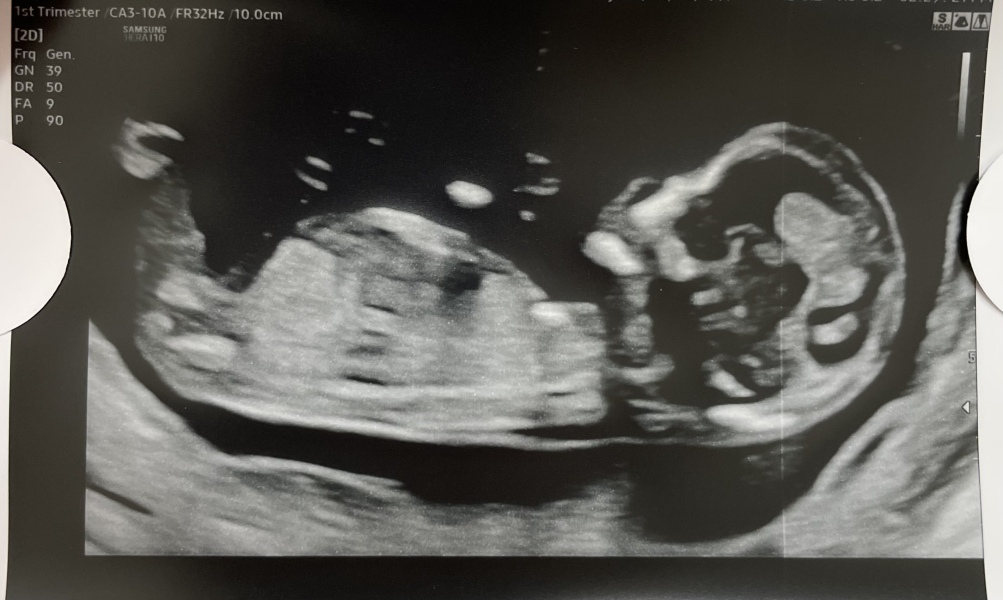

@Cassarat @xalexandra ALL GOOD! Baby was perfect, measuring ahead! Due 24th May xx

@Sprinklerainbows oh that's wonderful news! Congratulations!! I bet that was such a relief! 🥰 that is a lovely clear scan pic too!! Xx

@xalexandra well there was a collection of blood whcjh they saw when I was like 6 weeks but she said there’s absolutely nothing there now! Such a relief the lady was lovely, she couldn’t believe how much the baby was moving and only managed to get one pic 🤣 x